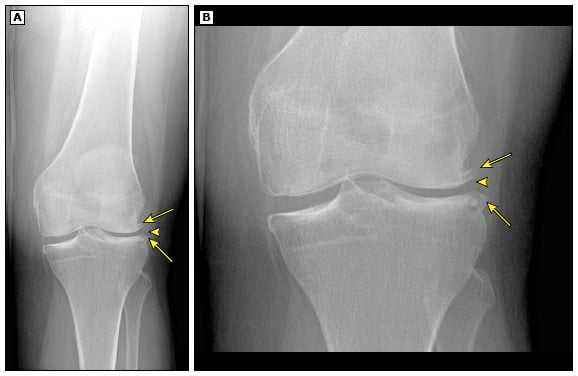

- рентгенография;